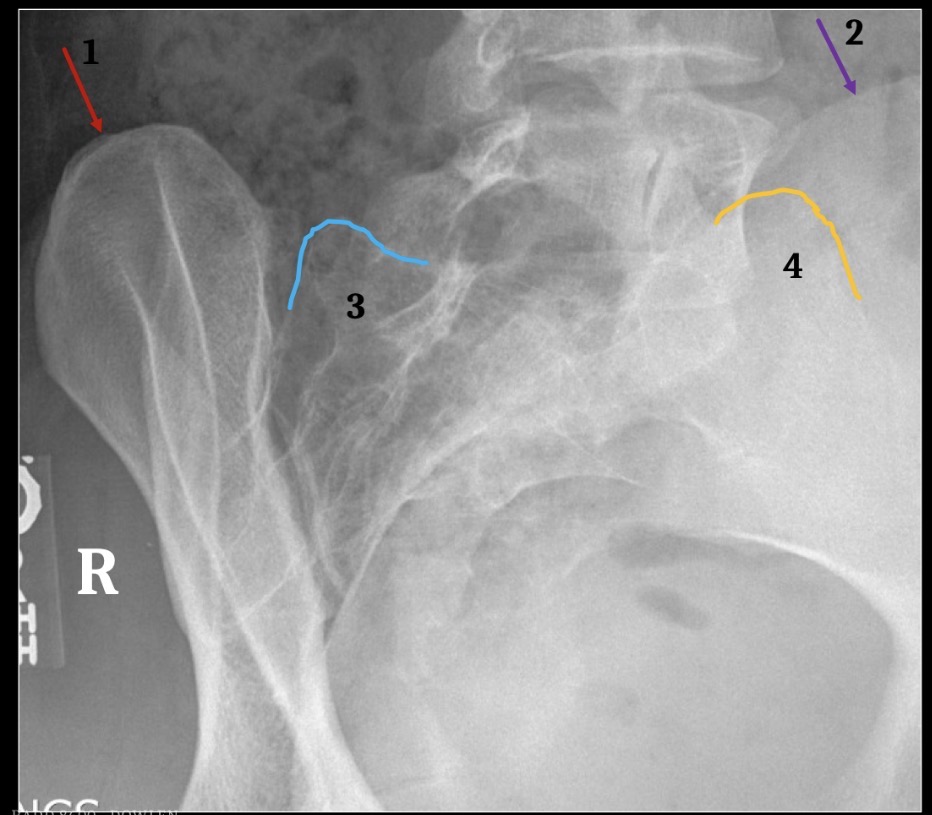

1

Right ilium

2

Left ilium

3

Right sacral ala

4

Left sacral ala